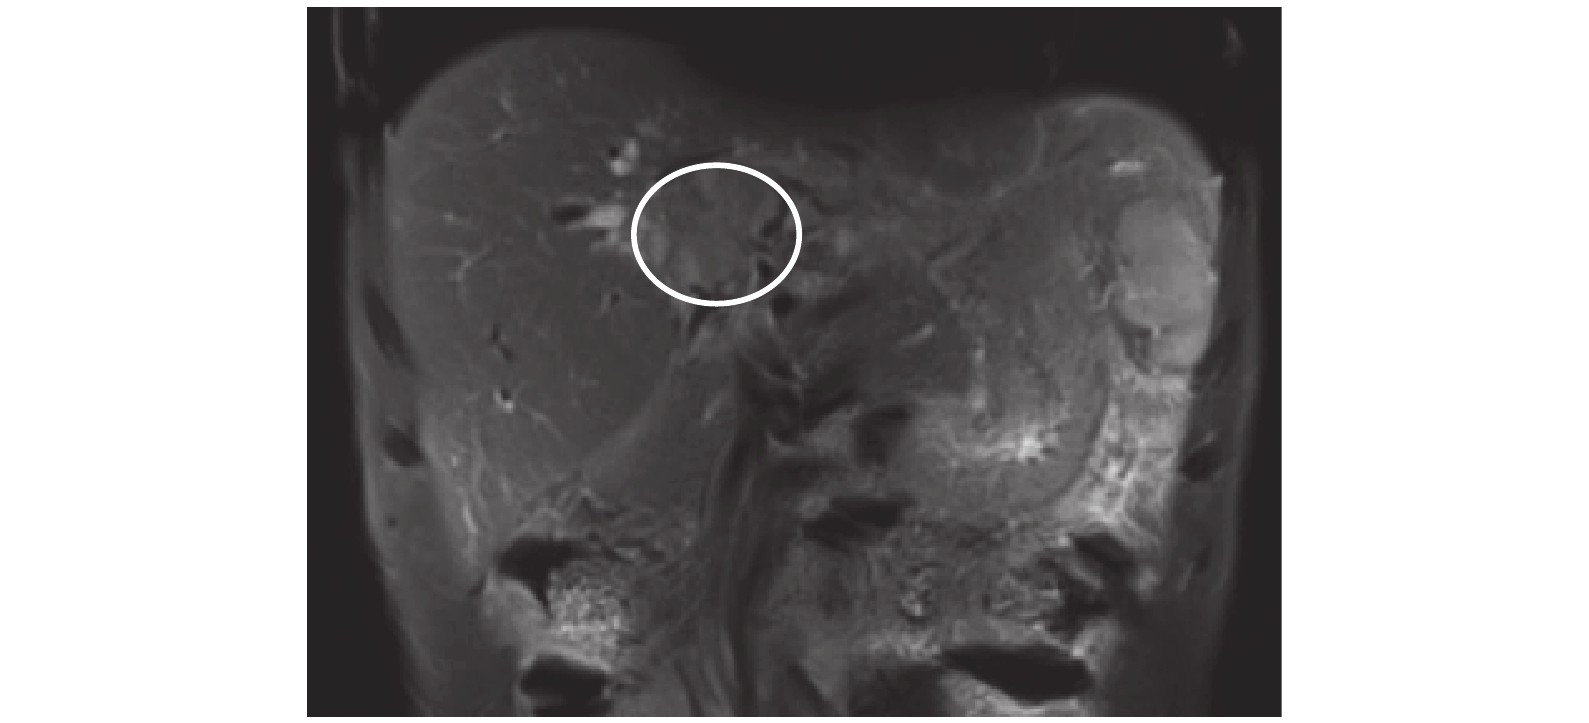

腹部彩超示:肝內膽管明顯擴張,左右肝管無法匯合;肝門區可見一 3.5 cm×2.5 cm 大的實性占位,肝實質內未見明顯占位病變。腹部增強 MRI 及水成像示:肝內膽管明顯擴張,肝門區可見一 3.7 cm×2.4 cm 大的實性占位,并向右肝管和左肝管內延伸,考慮肝門膽管癌可能性大(圖 1)。胸部 CT 及骨掃描未查見腫瘤轉移。